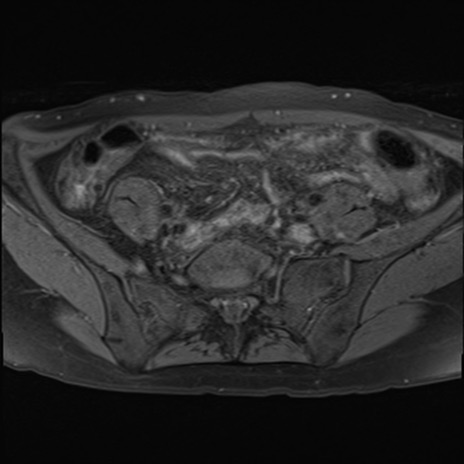

MRI(4日後)

T2WI(横断像)